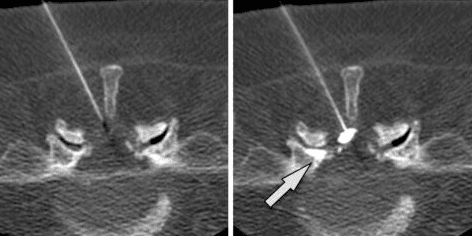

CT scan of a spine shows a needle targeting a spinal area, with an arrow indicating the entry point.

Step 4: Needle Targets Facet Joint

The needle is advanced until it reaches the facet joint capsule. Contrast dye may be injected to confirm proper needle placement within the joint space.